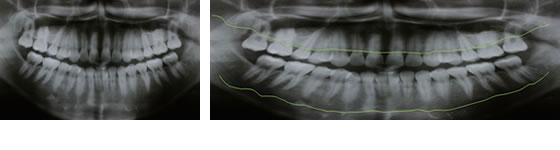

歯周病のレントゲン写真

ほぼ健康な方の骨の状態

ほぼ健常な方の骨の位置です。歯が骨の中に2/3位入っています。

状態:健常な状態

少し歯周病が進行された方の骨の状態

少し歯周病が進行してきた方の骨の位置。歯が骨の中に半分ほどしか入っていません。

状態:軽度(P1)、中度(P2)